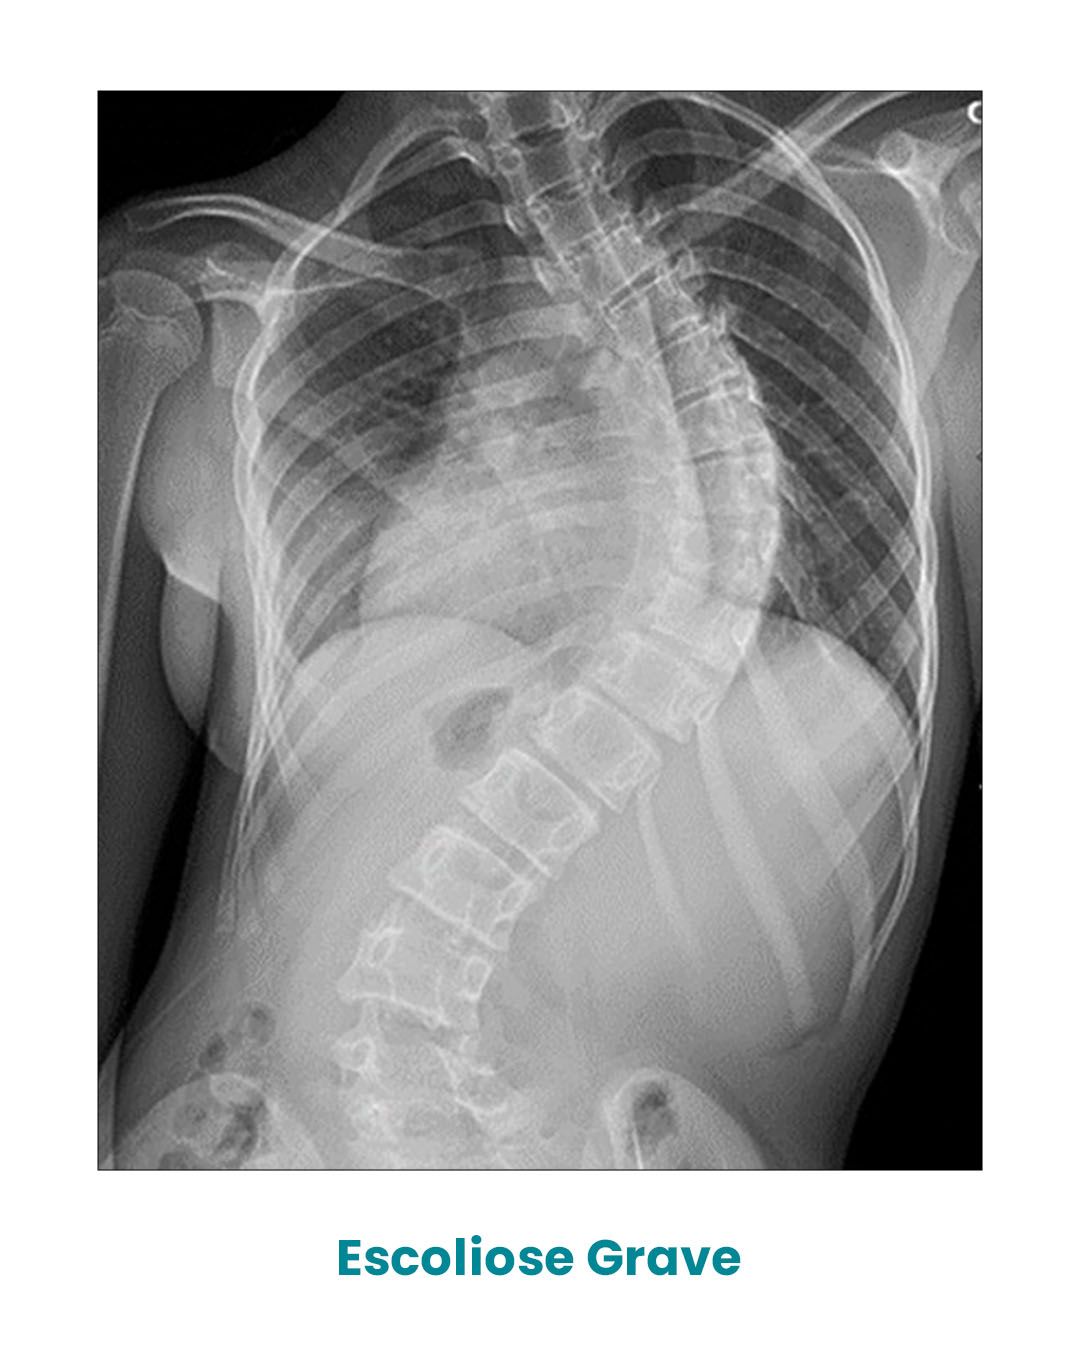

Após o diagnóstico, através de um simples Raio-X da coluna vertebral, podemos classificá-la em três tipos de acordo com o ângulo de Cobb.

Quando este ângulo ultrapassa os 50o, o caso é denominado de escoliose grave, sendo normalmente necessária à sua correção através de cirurgia.